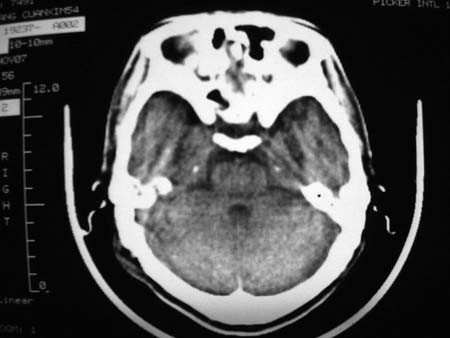

男,54岁,十天前被钢管打伤头顶部,现自述头部不适,视物模糊,并于两天前发觉右枕部有包块,既往未有明显异常.

颅骨多处骨质不完整,内板变薄,右侧额颞部局部呈“穿凿样”骨质缺损,相应区硬膜外密度略增高。多考虑:骨嗜酸性肉芽肿!

颅骨多处骨质不完整,内板变薄,右侧额颞部局部呈“穿凿样”骨质缺损,相应区硬膜外密度略增高。多考虑:骨髓瘤或骨嗜酸性肉芽肿!

颅骨多处骨质不完整,内板变薄,右侧额颞部局部呈“穿凿样”骨质缺损,缺损骨质边缘锐利无硬化,相应区硬膜外密度略增高。多考虑:骨嗜酸性肉芽肿!

颅骨多处骨质不完整,内板变薄,右侧额颞部局部呈“穿凿样”骨质缺损,相应区硬膜外密度略增高。多考虑:骨髓瘤或骨嗜酸性肉芽肿!10天前受伤,不会在2天前才发现头部包块,估计与外伤无关.